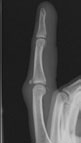

A central slip injury can be due to either a fracture at the base of the middle bone (avulsion) or from a tear in the fibres of the central slip itself (tendinous). You may need an x-ray to check if the bone is broken as well as the tendon being damaged. Your Hand Therapist, Physiotherapist or Occupational Therapist can organise an Xray referral for you. They will also assess your finger movement, swelling and pain in order to confirm the diagnosis.

An injury to the central slip is usually caused when the finger is traumatically forced into a bent position – for example being hit by a ball, or if the middle joint dislocates. An injury to your central slip tendon may result in a fixed flexion deformity which is an inability to fully straighten your finger, and puts you at risk of developing a deformity called a boutonniere.

Central slip injury, fixed flexion, Boutonniere deformity is caused by an avulsion or rupture of the central tendon in the finger. A forced bend or trauma to the finger can cause the Central slip to rupture.